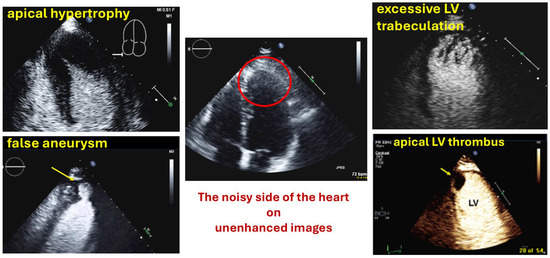

| Myocardial disease and masses |

| Thrombi |

| Apical hypertrophy |

| Pseudoaneurysm |

| Myocardial rupture |

| LV diverticula |

| Excessive LV trabeculations |

| Typical findings | Clear demarcation from the normal myocardium Narrow neck of false aneurysms Search for associated thrombi and pericardial effusion (more likely near false aneurysms) |

| Typical findings | 1. echofree mass 2. present in two different imaging planes 3. lump or laminar shape different from trabeculations’ documented size (two orthogonal diameters in at least one of the views), location, type (laminar vs. lump, single vs. multiple), surface (smooth vs. irregular) and mobility |

| Typical finding | 1. Hourglass/ace-of-spades shape of apical LV cavity 2. Apical myocardium appears dark in late systole due to compression of the intramyocardial vessels 3. Apical aneurysms +/− thrombi in some patients |

| Typical findings | trabeculated layer apical, lateral, and inferior: more than 3 trabeculations, ratio of trabeculated/compact myocardium >2 The number of trabeculations and the ratio of trabeculated/compact myocardium does not seem to impact clinical management |